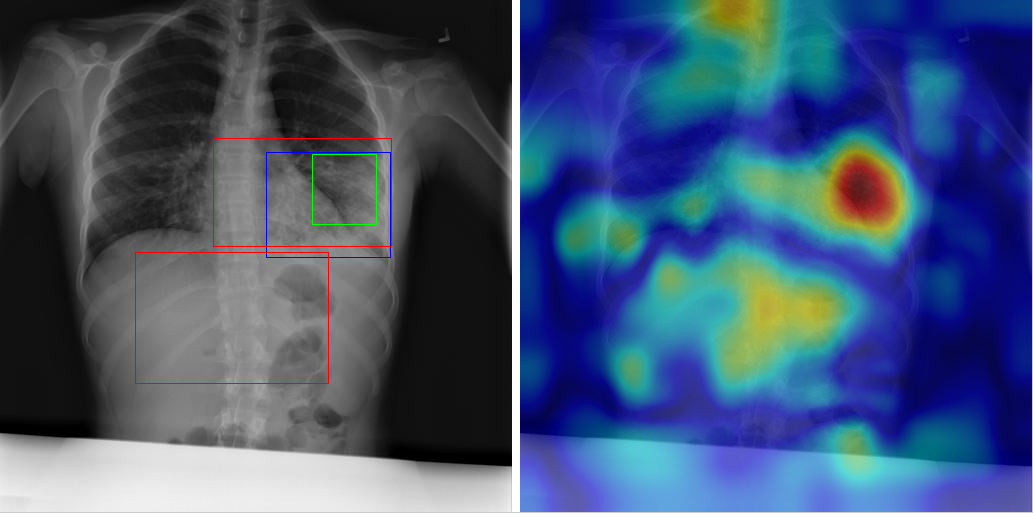

Table 8 to Table 15 illustrate localization results from each of 8 disease classes together with associated report and mined disease keywords. The heatmaps overlay on the original images are shown on the right. Correct bounding boxes (in green), false positives (in red) and the groundtruth (in blue) are plotted over the original image on the left.

In order to quantitatively demonstrate how informative those heatmaps are, a simple two-level thresholding based bounding box generator is adopted here to catch the peaks in the heatmap and later generated bounding boxes can be evaluated against the ground truth. Each heatmap will approximately results in 1-3 bounding boxes. We believe the localization accuracy and AFP (shown in Table 7) could be further optimized by adopting a more sophisticated bounding box generation method, e.g. selective search [47] or Edgebox [18]. Nevertheless, we reserve the effort to do so, since our main goal is not to compute the exact spatial location of disease patterns but just to obtain some instructive location information for future applications, e.g. automated radiological report generation. Take the case shown in Table 8 for an example. The peak at the lower part of the left lung region indicates the presence of “atelectasis”, which confer the statement of “…stable abnormal study including left basilar infilrate/atelectasis, …” presented in the impression section of the associated radiological report. By combining with other information, e.g. a lung region mask, the heatmap itself is already more informative than just the presence indication of certain disease in an image as introduced in the previous works, e.g. [42].

Radiology report Keyword Localization Result

findings: frontal lateral chest x-ray performed in expiration. left apical pneumothorax visible. small pneumothorax visible along the left heart border and left hemidiaphragm. pleural thickening, mass right chest. the mediastinum cannot be evaluated in the expiration. bony structures intact. impression: left post biopsy pneumothorax. Mass; Pneumothorax [Uncaptioned image]

Table 15: A sample of chest x-ray radiology report, mined disease keywords and localization result from the “Pneumothorax” Class. Correct bounding box (in green), false positives (in red) and the ground truth (in blue) are plotted over the original image.